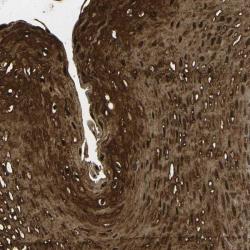

- Immunohistochemical staining of human esophagus shows strong cytoplasmic and nuclear positivity in squamous epithelial cells.

- Validation comment

- Two independent antibodies targeting one protein yielding similar staining patterns. Staining pattern consistent with experimental and/or bioinformatic data.